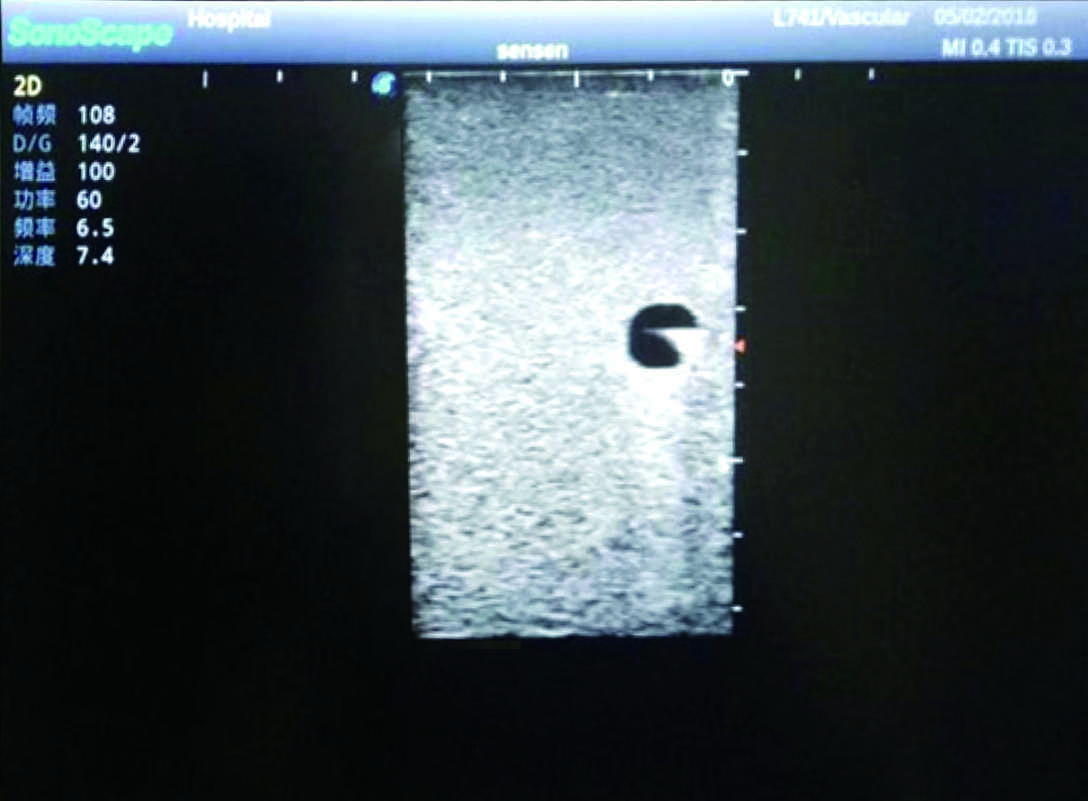

2) It can be used by real ultrasound machines

3) Clear and real images of the tissues and organs (basilic vein and superior vena cava)